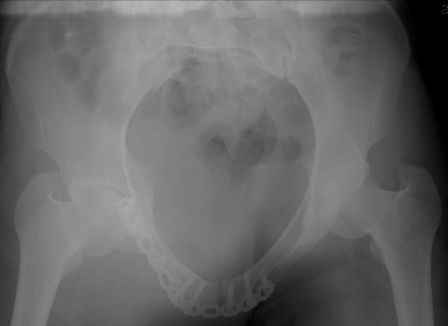

Серия до- и послеоперационных снимков этой пациентки. Хотя бы post factum обсудить. Не знаю, что можно сделать с задними отделами стержневым аппаратом, но три крепких парня открытым путем с помощью "волшебных" слов еле-еле смогли отрепонировать - сзади все было очень ригидно!